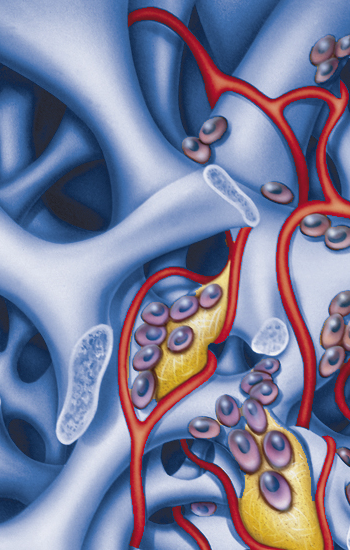

L’os humain est capable de se régénérer partiellement mais dans certains cas, ce processus exige un support. Les biomatériaux viennent renforcer la capacité naturelle de l’organisme à compenser la perte osseuse par la régénération de l’os.

Cet os nouvellement formé a besoin d’un échafaudage. Cet échafaudage sert à la fois de guide et de support. Un substitut osseux hautement poreux joue parfaitement ce rôle. Une membrane est quelquefois placée au-dessus de la zone osseuse traitée et stabilise le site pendant la cicatrisation. Elle empêche aussi les tissus mous, dont la prolifération est rapide, d’envahir cet espace pour permettre sa lente colonisation par l’os.